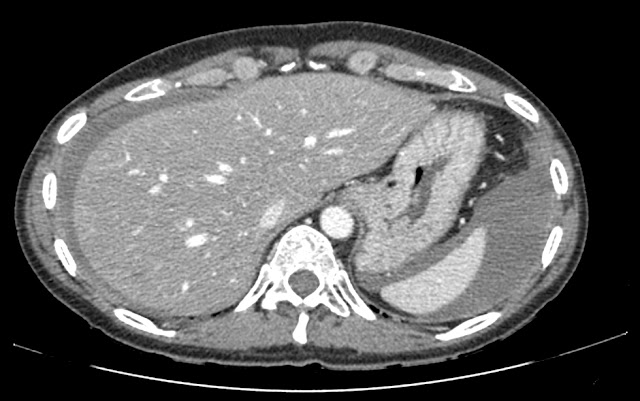

Cuerpo extraño en flanco derecho con marcados artefactos metálicos (perdigón?)

Esteatosis hepática con lesiones hipodensas en lóbulo hepático derecho. La de mayor tamaño se localiza en segmento VII, mide aprox. 2,7 cm y ecográficamente se corresponde con un quiste simple, pudiendo corresponder el resto lesiones con quistes aunque algunas de ellas por su pequeño tamaño no son posibles caracterizar definitivamente.

Líquido libre de moderada cuantía a nivel perihepático, periesplénico en ambas goteras paracólicas y en pelvis, identificando discreta alteración de la grasa en ambos hipocondrios y alguna pequeña lesión nodular, altamente sugestivo de carcinomatosis peritoneal.

El líquido localizado en ambas goteras paracólicas y en pelvis presenta una densidad alta en el rango del líquido complicado, que obliga a descartar hemoperitoneo.